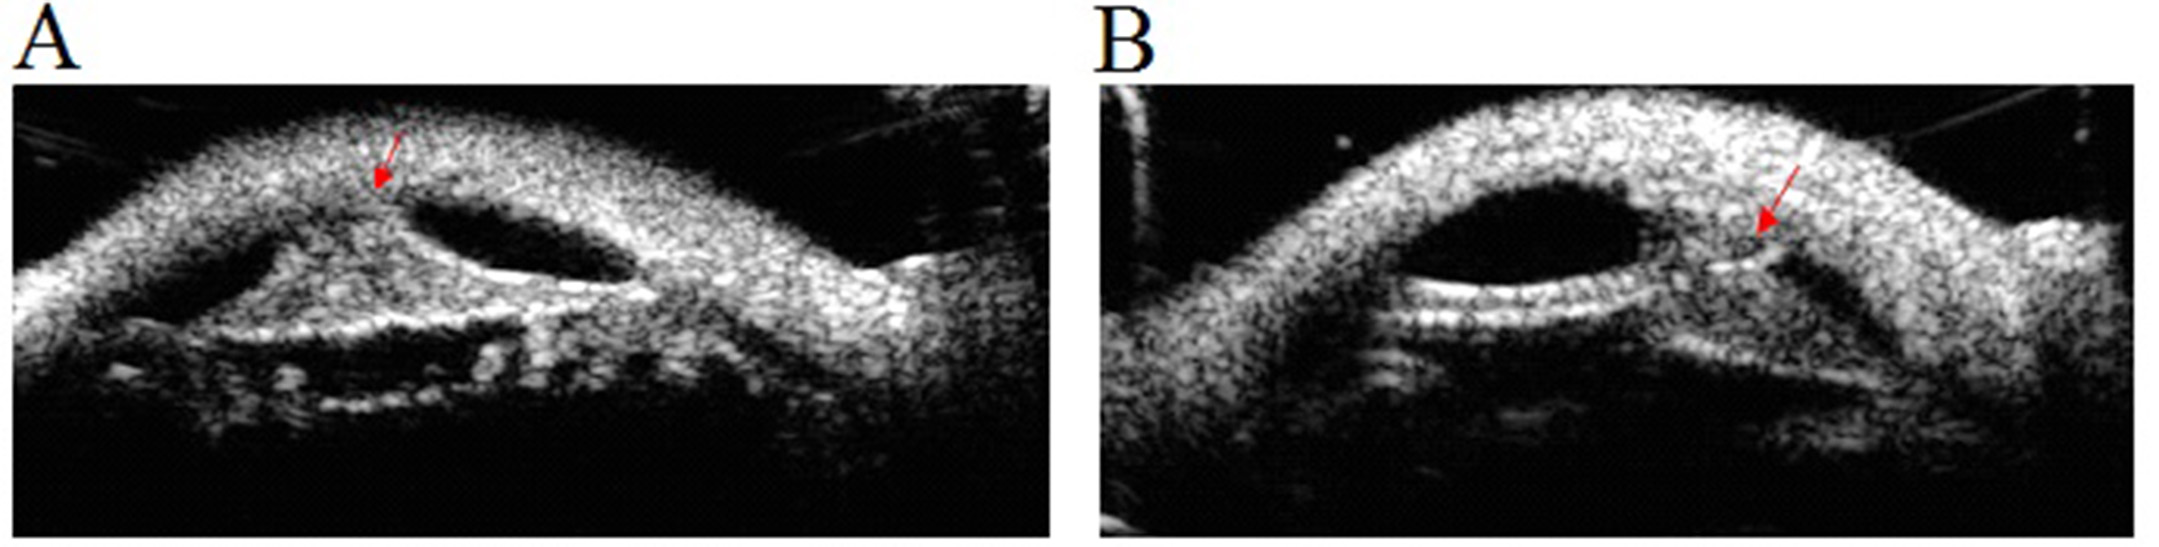

Figure 3 of Darbari, Mol Vis 2020; 26:757-765.

Figure 3. Ultrasound biomicroscopy images show the Peters anomaly. A: PA-101-VI4. B: PA-101-VI5. Images of both patients show iridocorneal adhesion (arrows).